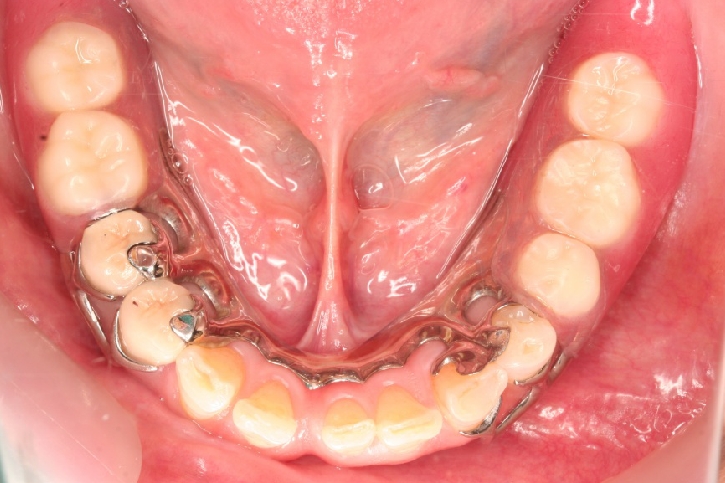

義歯修復

担当歯科医師:川津良介

2013年3月6日千葉県市原市 M.K様  金属床義歯修復